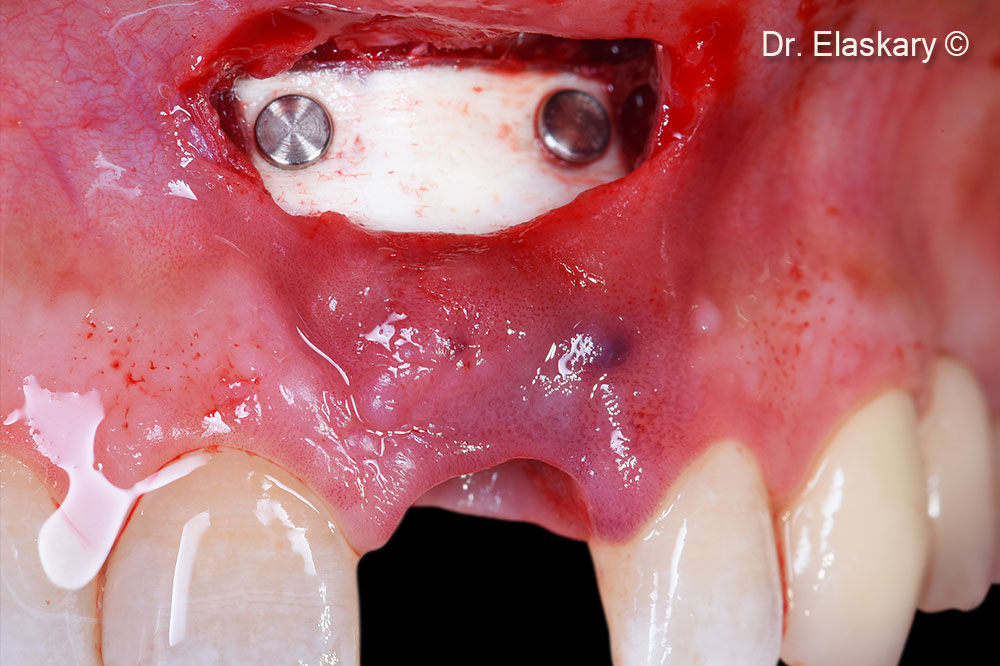

Lamina® 1 mm is stabilized using two membrane tacs apically